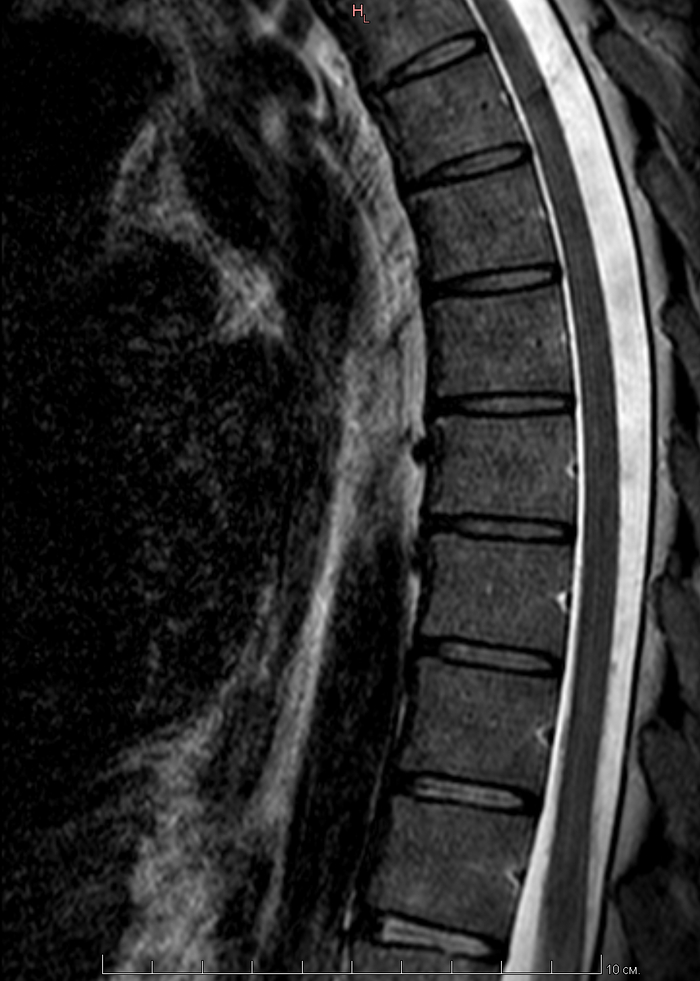

МРТ всех отделов позвонка

К этому посту Мое первое МРТ в 32 годика и этому Пикабу, нужна помощь по здоровью(Невролога(Но это не точно))

Пришло заключение от МРТ центра, я понимаю что надо идти еще на консультацию невролога и т.д. Но может кто из пикабушников сможет расшифровать по нашему, что и как.

Ну и что мне дальше делать.

Делал я МРТ всех отделов позвоночника. Лежал в аппарате полтора часа.

По самому МРТ, может кто тут разбирается, я приложу пару снимков, так как заключение будет только в понедельник. Может кто и поможет. Но, как сказала врач в центре МРТ, с моей симптоматикой, надо делать МРТ головного мозга =(